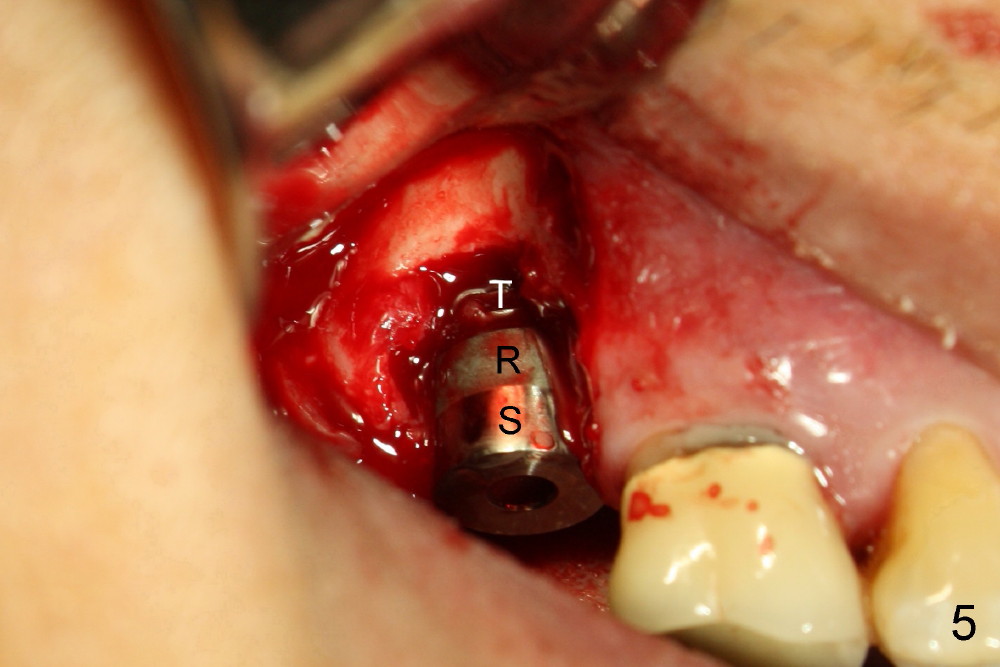

The 60-year-old man is a bruxer. All of the three upper right molars are nonsalvageable (Fig.1). Since #2 is symptomatic, it is planned to be extracted and restored first. As expected, there is severe alveolar destruction (single large socket), while the base bone is solid. A series of tapered osteotomes (2-5 mm) are used to create osteotomy in the base bone (gaining 4 mm into new bone), followed by 4.5x20 mm tap at the depth of 17 mm from the gingival margin (Fig.2). Then the depth is adjusted to 14 mm; the bone expansion and osteotomy continue until using 7 mm tap with good binding to the bone (Fig.3). A 7x14 mm implant is placed with insertion torque more than 60 Ncm (Fig.4). No bone graft is used for sinus lift considering sinus membrane perforation. The buccal flap is raised to reveal bony defect, which is covered by Osteogen (a synthetic bone graft) and then collagen membrane (Fig.6 *). Five days postop, the membrane undergoes a type of transformation (Fig.7 *) leading to a gingival tissue (Fig.8 *, 18 days postop). By 3 months, the gingiva has normal appearance (Fig.9), while the implant seems to be osteointegrated (Fig.10). Once the infected source is removed, our body has potential to regenerate.